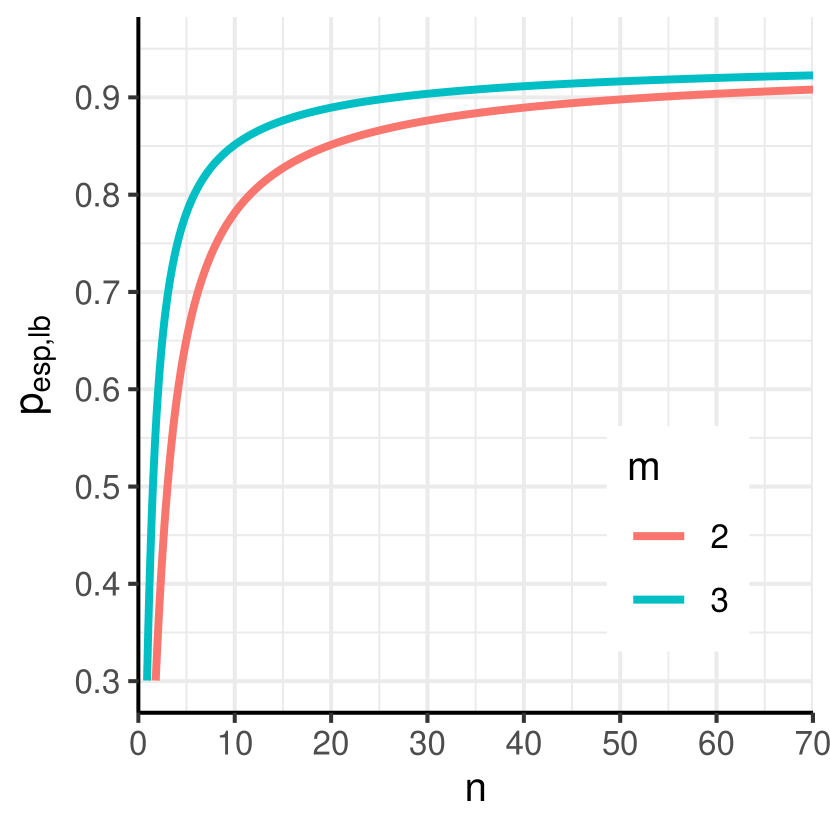

This can also be concluded from Figure 4 A. Numerical solution of the exact formula (16) yields a sample size of 54. Resulting sample sizes for other values of can be taken from Figure 4 B. The resulting scenario in terms of the distribution of the relative error in the estimation of and its effect on is displayed in Figure 5 A.

B) Sample size resulting from (16) for different values of the desired lower bound that shall be exceeded with a fixed confidence of 95%.

Common sample sizes in test-retest studies are around 10 and 20 [3, 12, 22, 15, 4, 21]. If the point estimator of resulting from a test-retest study with a sample size of 10 and two repeated measurements is used, the distribution of the effective specificity will have prominent tails as illustrated in Figure 1. According to (17), the lower bound of the effective specificity obtained with 95% confidence is 0.7814 and 0.8512 for a sample size of 10 and 20, respectively, which might be insufficient (Figure 4). Note that for the recommendation by Obuchowski and Bullen[24] of a sample size of 35 for test-retest studies with the probability of achieving an effective specificity below 94% is 39.74%.

While our formulas enable flexible calculations for all scenarios, for convenience of the reader we also provide a table with sample sizes for some exemplary scenarios in Figure 4. Sample sizes resulting from other choices of the parameters , , and can be found in Supplementary Tables S1-S4.